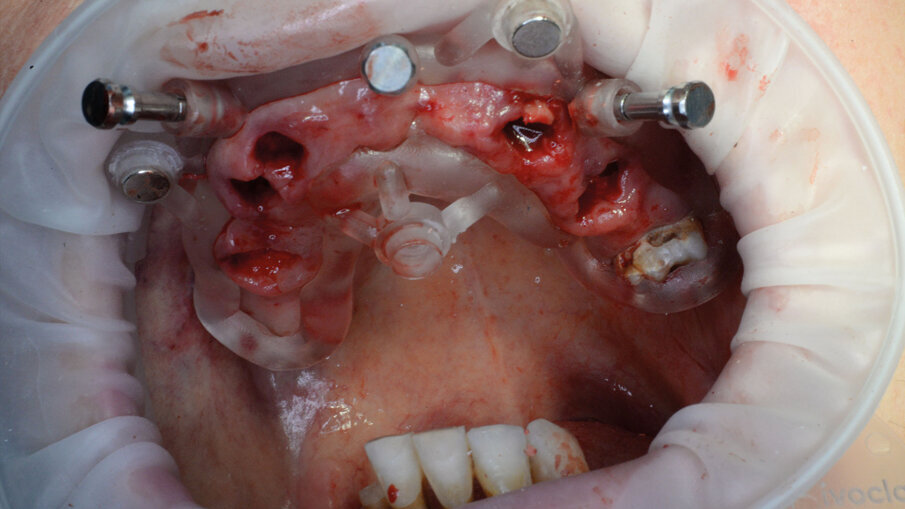

Per la realizzazione delle dime chirurgiche abbiamo utilizzato il nuovo modulo Sculpt rilasciato per lo stesso software di chirurgia guidata BNX 3D GUIDE. Questo nuovo modulo permette di creare una serie di dime scomposte da utilizzare in sequenza per eseguire le estrazioni e l’osteoplastica necessaria, rimanendo sempre all’interno di un flusso di lavoro guidato. Le dime si adattano l’una all’altra grazie a supporti di accoppiamento che contengono piccoli magneti con polarità opposta. L’azione di questi magneti permette di ritrovare velocemente e fedelmente sempre la stessa posizione delle dime anche se dovessimo rimuoverle per poi reinserirle. Affidandoci alla stabilità ancora presente su alcuni denti abbiamo progettato una prima dima ad appoggio dentale che permettesse il corretto posizionamento della dima esterna che sarà l’unica a rimanere sempre in posizione fino alla fine dell’intervento (Fig. 9). Una volta stabilizzata con i pin di stabilizzazione e rimosso il posizionatore, si è potuto apprezzare la bellezza della metodica che permette un’ampia visione e molto spazio a disposizione per poter eseguire le fasi chirurgiche preliminari di preparazione (estrazioni e sollevamento di piccoli lembi). Liberata l’arcata dall’ingombro dei denti e di tessuti in eccesso si è potuto posizionare la dima di perforazione nella corretta posizione grazie alla presenza della dima esterna rimasta in posizione (Figg. 10-13).

Alla preparazione dei tunnel implantari è seguito il loro inserimento sempre con tecnica guidata utilizzando gli appositi montatori forniti nel kit, avendo cura di far combaciare le tacche di riferimento dei montatori con le linee di repere preventivamente disegnate sulla dima così da ottenere il corretto posizionamento dei 2 mua angolati previsti nel settore anteriore (Fig. 14). In fase chirurgica il posizionamento dei mua è stato ulteriormente facilitato dalla presenza di un doppio esagono presente all’interno dell’impianto che rende possibili ulteriori aggiustamenti “di fino” del componente protesico. Avvitate tutte le torrette il provvisorio è stato poi cementato con cemento duale dedicato utilizzando un foglietto di diga preforato per facilitarne la cementazione (Figg. 15, 16).